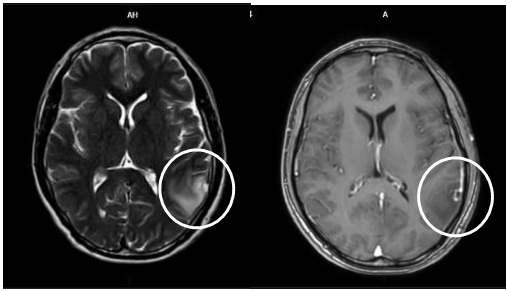

- Cộng hưởng từ sọ não:

Hình ảnh nốt ngấm thuốc vỏ não thùy thái dương trái kèm phù não rộng xung quanh kích thước 7x8mm (vòng tròn màu trắng) do di căn

So sánh hình ảnh cộng hưởng từ sọ não trước và sau điều trị 8 tháng

Sau 9 tháng điều trị: U phổi giảm kích thước, hạch trung thất không còn, tổn thương di căn não đơn ổ biến mất, chất chỉ điểm khối u CEA, Cyfra 21-1 giảm về giới hạn bình thường. Bệnh nhân không gặp tác dụng phụ đáng kể nào trong quá trình điều trị.